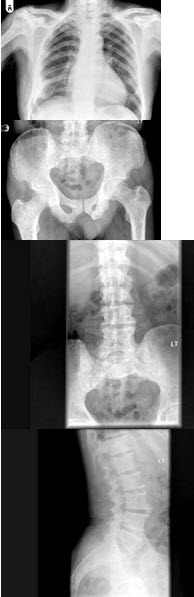

28、单项选择题

男,65岁,腰背部疼痛1月余,结合图像,最可能的诊断是()

A.脊椎结核

B.椎体压缩骨折

C.脊椎退行性变

D.脊椎转移瘤

E.L2~L3椎间盘炎

159、单项选择题

男,77岁,全身性骨痛,夜间加重,贫血,PSA大于100,结合图像,最可能的诊断是()

A.成骨性骨转移

B.多发性骨髓瘤

C.慢性化脓性骨髓炎

D.骨肉瘤

E.以上都不是

297、单项选择题

男,60岁,因双髋关节反复疼痛2年余,无明显外伤史,X线摄片如图,最可能的诊断是()

A.双髋关节退行性骨关节病

B.双髋关节创伤性关节炎

C.双髋关节特发性骨关节病

D.双髋关节结核

E.神经性关节炎